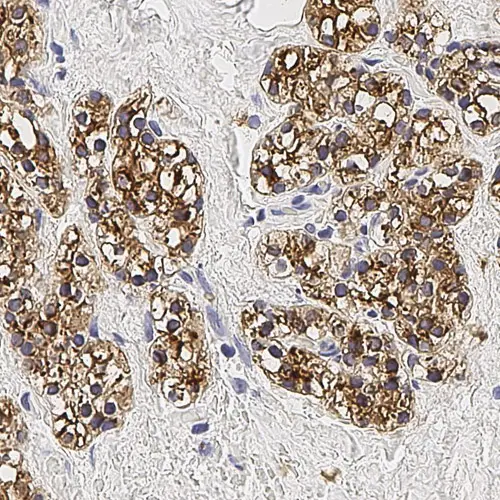

Human parathyroid adenoma: immunohistochemical staining for Parathyroid Hormone. Note membrane/cytoplasmic staining of tumor cells. Parathyroid Hormone: clone 105G7

The parathyroid glands are small, oval, endocrine glands closely associated with the thyroid gland. The parathyroid glands regulate serum calcium and phosphate levels via parathyroid hormone (parathormone). Parathyroid hormone raises serum calcium levels directly, by increasing the rate of osteoclastic reabsorption and promoting breakdown of the bone matrix, and indirectly, by increasing the renal tubular reabsorption of calcium ions and inhibiting the reabsorption of phosphate ions from the glomerular filtrate, and finally, by promoting the absorption of calcium from the small intestine. Parathyroid hormone is the most important regulator of blood calcium levels and is essential to life, whereas calcitonin appears only to provide a complementary mechanism for fine adjustment. Chief cells are the most abundant cells in the parathyroid gland and are responsible for the secretion of parathyroid hormone.

Parathyroid Hormone (PTH) is recommended for the detection of specific antigens of interest in normal and neoplastic tissues, as an adjunct to conventional histopathology using non-immunologic histochemical stains.